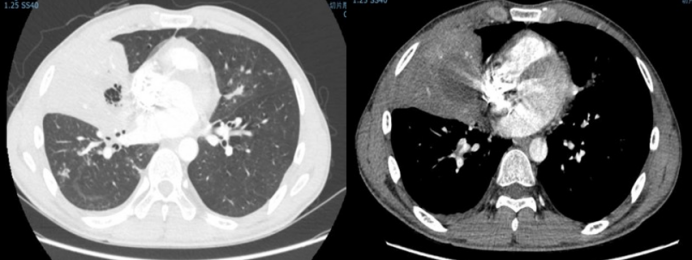

病例4:一例白血病合并毛霉感染患者。影像学检查可见胸膜下反晕征及空气新月征(图4)。该患者经内科治疗病情好转后,接受了手术切除治疗,但术后2周出现感染再次播散,最终不幸死亡。此病例表明,即使采用内科治疗联合手术切除的传统方案,肺毛霉病仍可能因感染播散导致不良结局。

图片

图4  病例4手术前后胸部CT